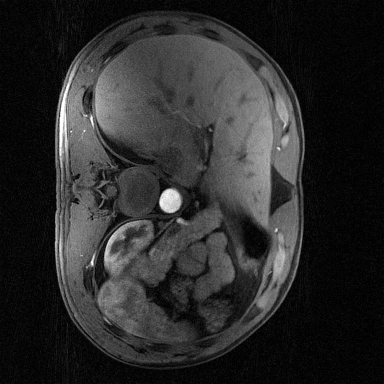

Supervised Deep-Learning (DL)-based reconstruction algorithms have shown state-of-the-art results for highly-undersampled dynamic Magnetic Resonance Imaging (MRI) reconstruction. However, the requirement of excessive high-quality ground-truth data hinders their applications due to the generalization problem. Recently, Implicit Neural Representation (INR) has appeared as a powerful DL-based tool for solving the inverse problem by characterizing the attributes of a signal as a continuous function of corresponding coordinates in an unsupervised manner. In this work, we proposed an INR-based method to improve dynamic MRI reconstruction from highly undersampled k-space data, which only takes spatiotemporal coordinates as inputs. Specifically, the proposed INR represents the dynamic MRI images as an implicit function and encodes them into neural networks. The weights of the network are learned from sparsely-acquired (k, t)-space data itself only, without external training datasets or prior images. Benefiting from the strong implicit continuity regularization of INR together with explicit regularization for low-rankness and sparsity, our proposed method outperforms the compared scan-specific methods at various acceleration factors. E.g., experiments on retrospective cardiac cine datasets show an improvement of 5.5 ~ 7.1 dB in PSNR for extremely high accelerations (up to 41.6-fold). The high-quality and inner continuity of the images provided by INR has great potential to further improve the spatiotemporal resolution of dynamic MRI, without the need of any training data.

翻译:在这项工作中,我们建议了一种基于IRI的方法,用这种方法来改进动态磁共振感应成像(MRI)重建,而该方法只是以高度低劣的 k-空间数据为基础,而该数据仅以磁共振坐标作为投入。具体地说,拟议的IRI将动态MRI图像作为一种隐含功能来表示,并将其编码到神经网络中。网络的权重仅从稀有的(k, t)空间数据本身中学习,而没有外部培训数据集或先前的图像。 利用基于IRI的强有力隐含性稳定化,同时不以清晰的动态和时空坐标坐标坐标坐标坐标作为投入。 拟议的IRIR将动态MRI图像作为一种隐含功能,将其编码到神经网络中。网络的权重仅从淡化的(k, t)空间数据本身学习,而没有外部培训数据集或先前的图像。